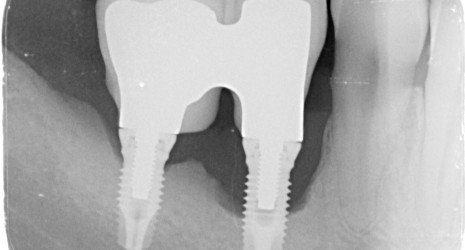

Tratamiento de la perimplantitis

En los últimos años el boom de la implantología ha llevado a la colocación de implantes de manera indiscriminada en situaciones donde no estaba indicado.

Se está observando un creciente aumento de la prevalencia de implantes afectados por infecciones llamadas perimplantitis. Estas cursan con grandes destrucciones de hueso alrededor de los implantes.

Como especialistas en el campo de la periodoncia en Clínica Villar estamos especialmente cualificados para el tratamiento de estas infecciones.